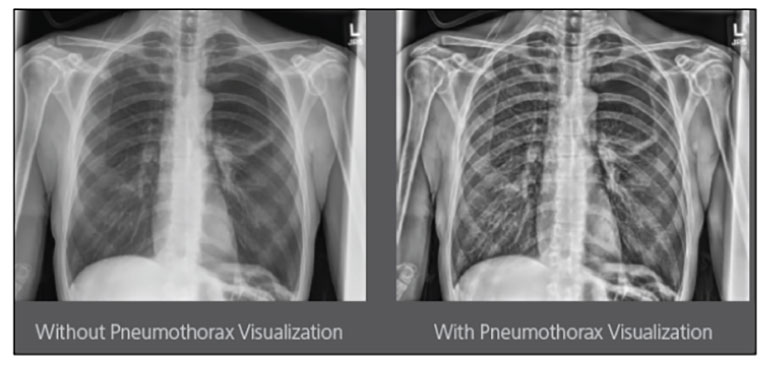

CARESTREAM Image Suite V4 MR11 has set a new standard for workflow efficiency, offering a robust set of features and functionalities to enhance clinical confidence in healthcare professionals. Using an auto-generated companion image from a single exposure, leverage a range of image processing options to increase diagnostic accuracy and enhance patient care.